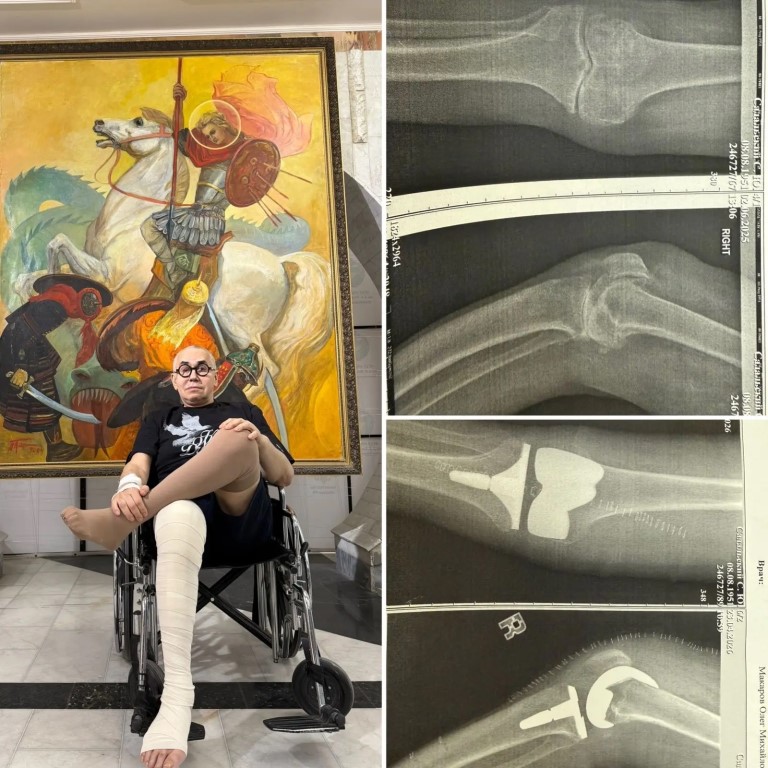

Фото «Я уже не ползаю по сцене»: Садальский показал последствия серьезной операции Всенародно любимый актёр Станислав Садальский, выросший в воронежском интернате, рассказал о перенесенной им операции в военном клиническом госпитале Вишневского. Там Садальскому провели протезирование коленного сустава. - У меня огромная радость, я уже не ползаю по сцене и странно не хожу. Робот с «глазами» из госпиталя Вишневского выполнил протезирование коленного сустава на отлично! Потрясающие хирурги задавали ему команды, которые мгновенно исполнялись, - рассказал артист.